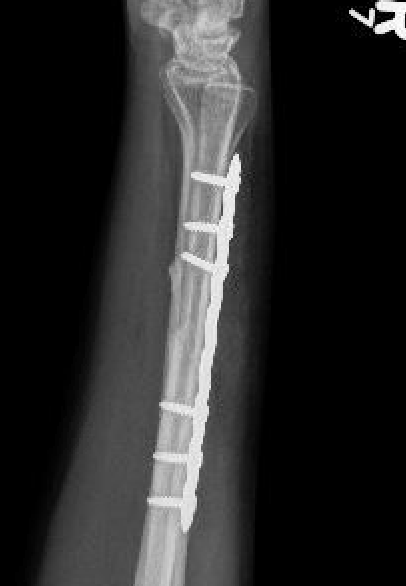

Compression plating

Intra-medullary nail

Ulna Intramedullary WireUlna Plating

Technique

AO foundation ulna plating

Complications

nonunionnonunion

Ulna nonunion after plating